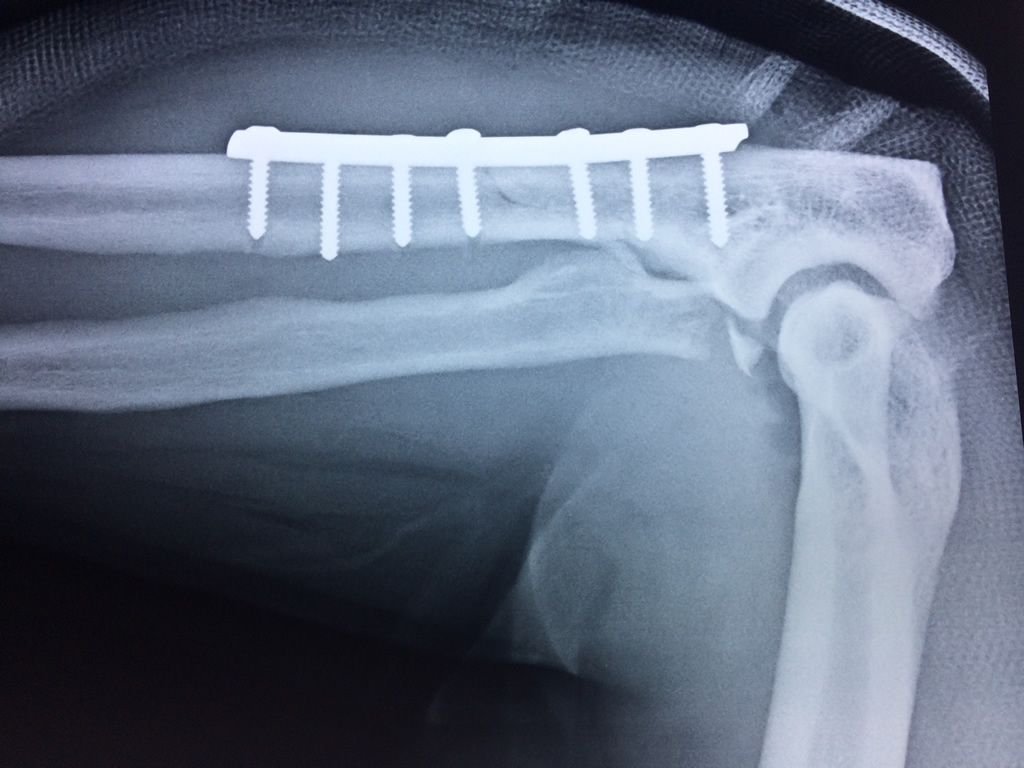

Cirugías de Calcaneo - Codo